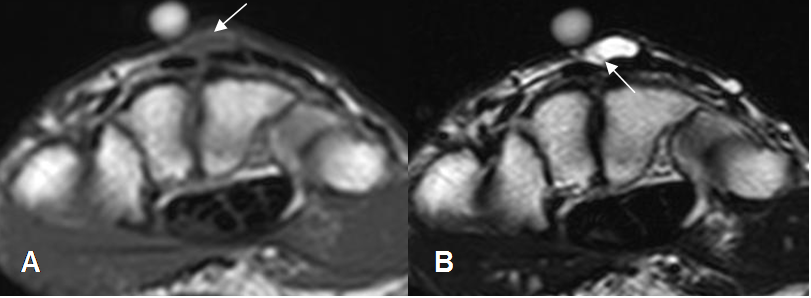

Fig 218 B. Ganglión quístico.

A: RM axial en T1 y B: RM axial en T2. Lesión isointensa en T1 e hiperintensa en T2 en el dorso del carpo, por ganglión.

Se observa septo delgado en T2. (Flecha).